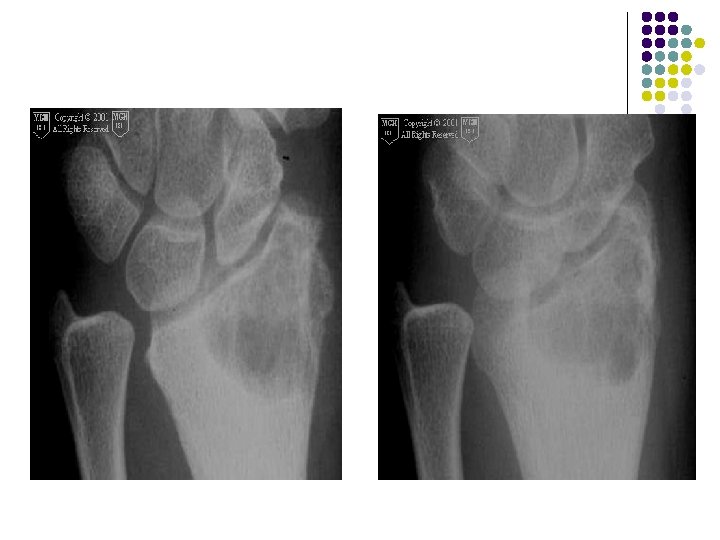

Case - 1 l A young boy of 11 years presented with c/o wrist pain WITHOUT any significant soft tissue swelling.

Radiographic Findings: Wrist Films: l Lobulated lytic lesion of the distal radius abutting the articular surface and extending from the epiphysis into the proximal metaphysis. l matrix calcification are seen. MR: l The lesion demonstrates low signal on T 1 weighted images and high signal on T 2 weighted images with rings and arcs compatible with chondroid matrix. l No extra-osseousoft tissue mass is seen.

Diagnosis l Chondroblastoma

Lucent area with well-defined margins in region of epiphysischondroblatoma in 11 yrs old boy Coronal reconstructed ct Coronal t 1 confirmsmetaphyseal weighted extension

AP radiograph of the left wrist shows an expanded solitary lytic lesion involving closed epiphyses subarticular position of the distal ulna without rim of sclerosis or periosteal reaction which is typical for a giant cell tumor

Giant cell tumor of distal radius is eccentric and extend to the end of the bone